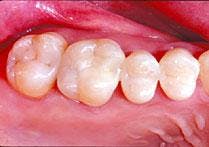

Regarding posterior composites, all - and I mean all - decay and soft dentin and decalcified enamel must be removed. This is a zero-tolerance consideration!

There is no toxic biofilm to save you here. Bonding has to be precise! Bonding over an unknown micro-junk pile - similar to current "sealant" theory - is a fantasy fix. No amount of sixth - or any generation - agent will help you, nor will a high-output laser help you. You are on your own, chum!